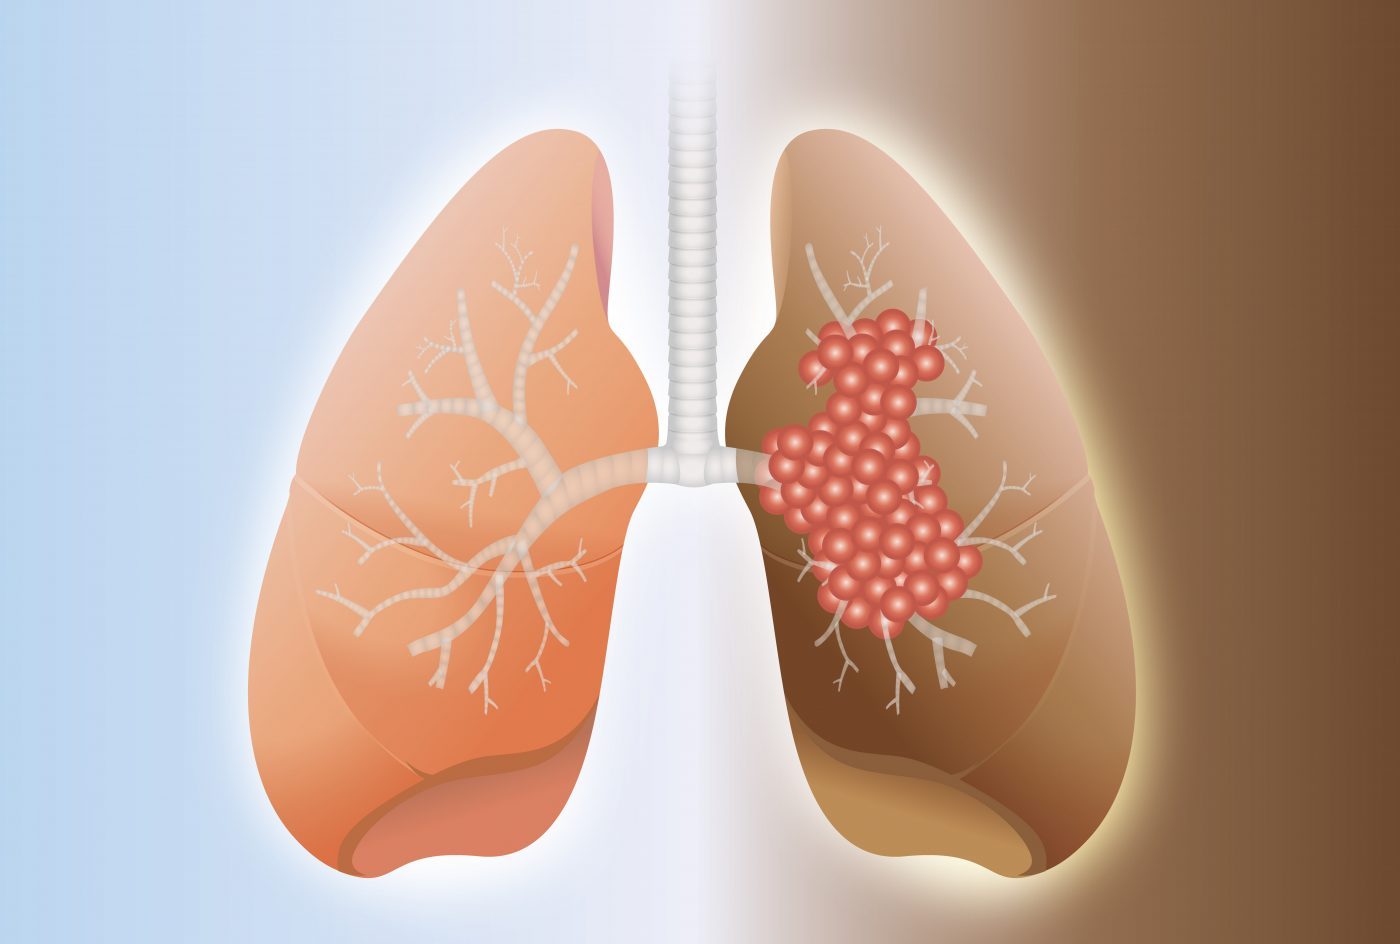

التليف الرئوي مجهول السبب هو مرض رئوي مزمن يسبب ندبات تدريجية في الرئتين، حيث تتبادل الحويصلات الهوائية الأكسجين وثاني أكسيد الكربون في الرئتين السليمتين، ولكن في التليف الرئوي مجهول السبب، تصبح هذه الحويصلات الهوائية سميكة ومتصلبة بسبب تكوين نسيج ندبي، مما يجعل من الصعب مرور الأكسجين، كما وجد في دراسة نشرتها StatPearls.

ويؤدي هذا إلى ضيق في التنفس والسعال الجاف والتعب، والتي تزداد سوءًا بمرور الوقت، في حين لا يوجد علاج للتليف الرئوي مجهول السبب، يمكن أن تساعد بعض الأدوية والعلاجات في إبطاء تقدم المرض وإدارة الأعراض.